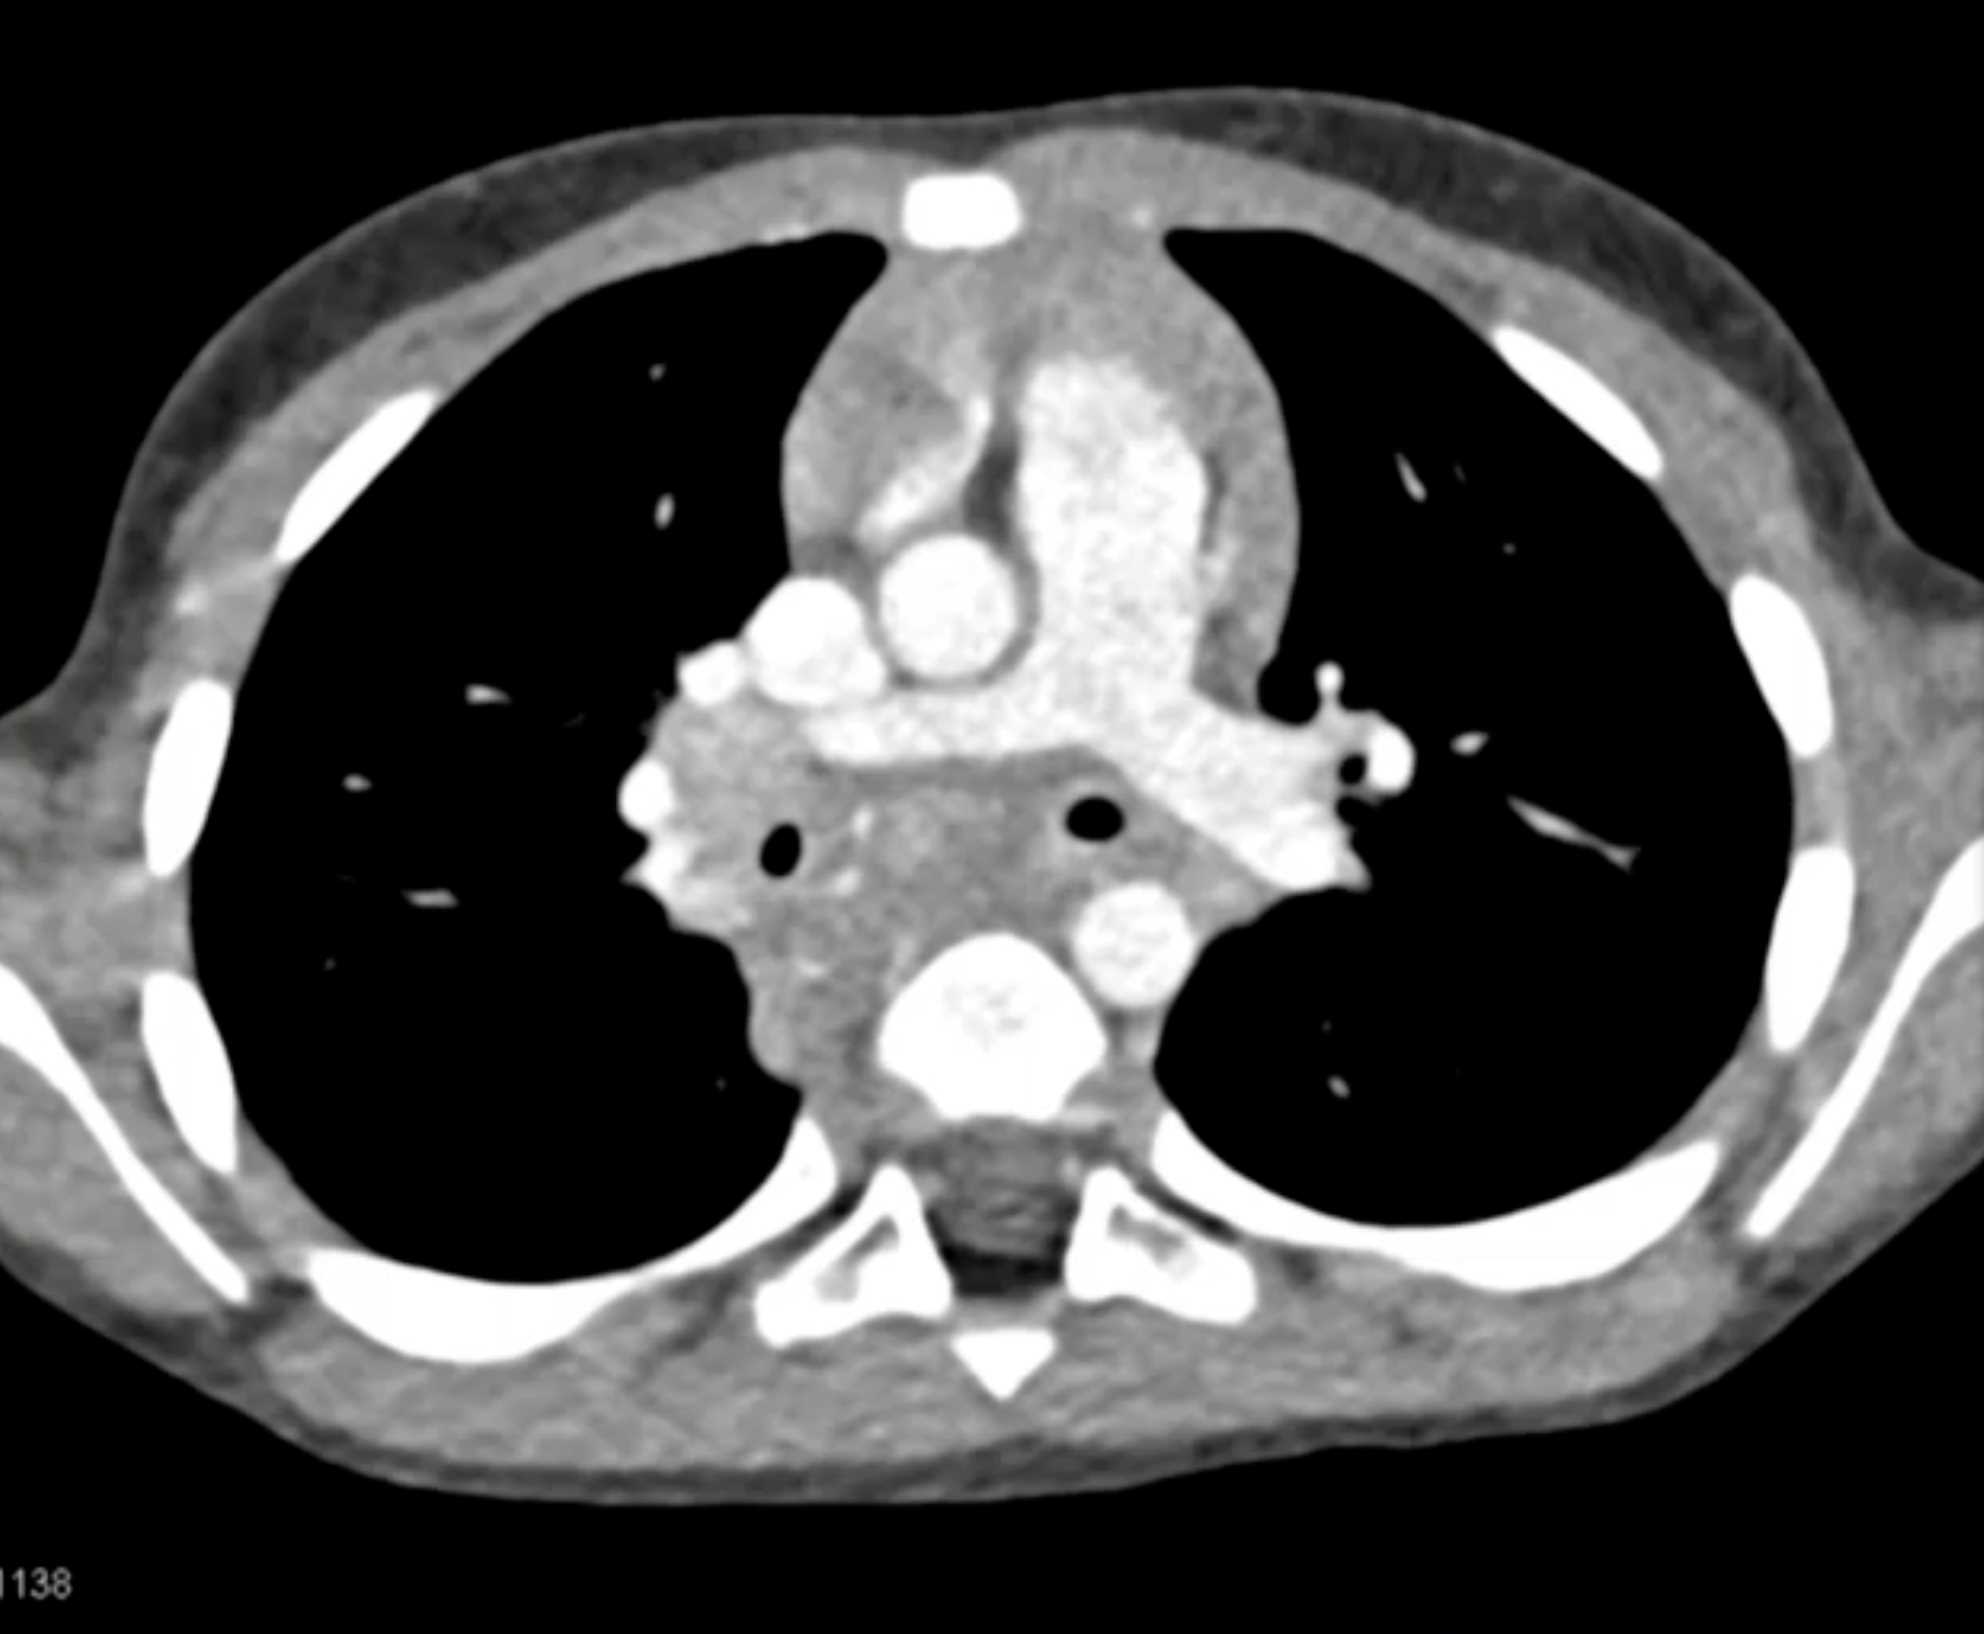

Histoplasmosis and Normal Thymus